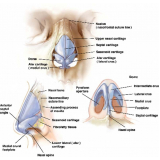

Conheça os procedimentos de excelência para a realização de uma cirurgia plástica a laser!